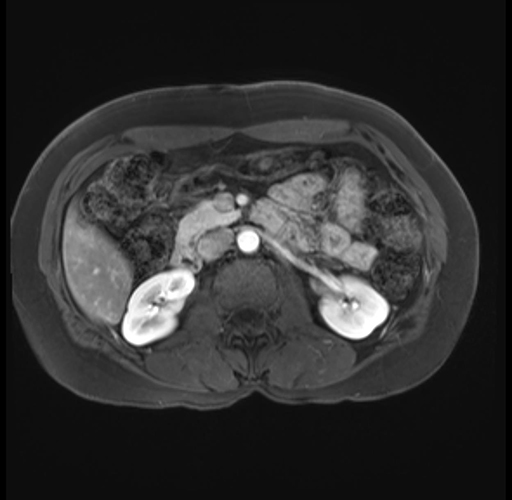

Imaging Analysis

Look through the patient's CT scan to identify any areas of concern for the necessary procedure.

Based on your CT findings, which issue(s) are present and would give reason for "planned slowing down moment(s)" in this case?

Considering a standard distal pancreatectomy procedure, what step(s) of the operation would you do differently in this case?